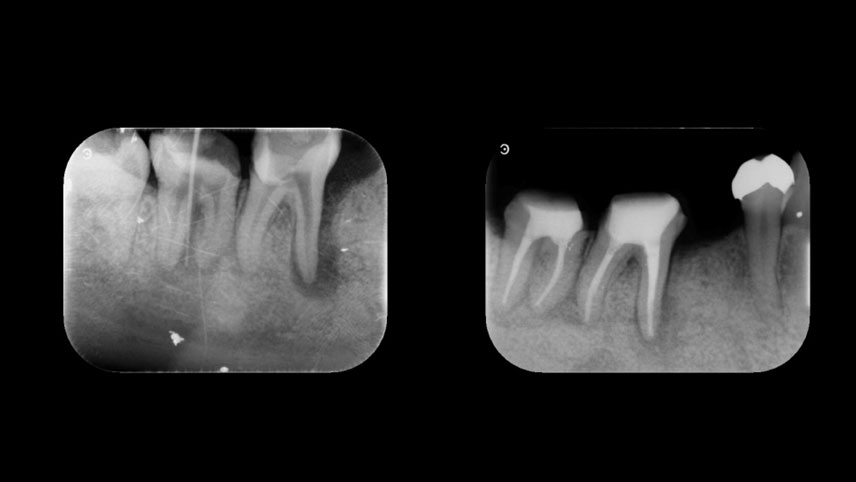

症例1 歯周病で抜歯と

言われた歯の保存

• 主訴

歯がグラグラ動く

• 診断

重度歯周病

• 治療

歯周基本治療、歯周組織再生療法

• 治療期間

8ヶ月

• 治療費

約12万円

• リスク

再発の可能性あり

※歯周組織の再生量は個人差があります。

歯周病で抜歯と言われた歯の保存

before    after